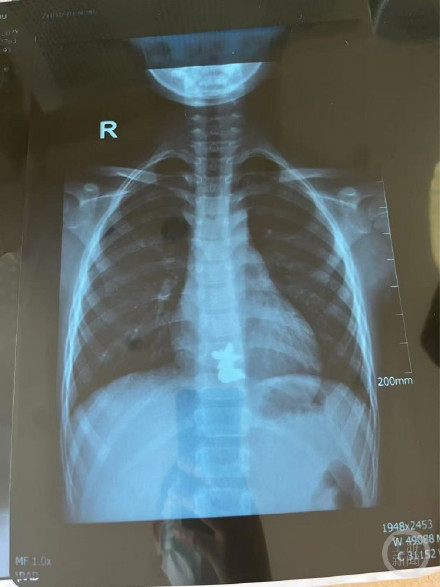

该院消化科主治医师杨丽燕介绍,患儿的年龄大多在6岁半到10岁之间。其中3个孩子吞服队徽后卡在食道里,消化科医生通过急诊胃镜取出,还有一个孩子因吞服两枚磁铁,出现肠穿孔,情况严重,由普外新生儿外科医生进行紧急手术。

“腹腔镜进去后,发现第一枚磁铁是在升结肠的位置,第二枚磁铁在距离小肠的末端——距离回肠大概五六十厘米的地方,两枚磁铁紧紧地吸在一起,中间还夹住了一块小肠。”主刀医生普外新生儿外科袁亮主治医师回忆,取下磁铁后,又发现天天有四处肠穿孔,只有将坏死的肠管进行切除后缝合,“磁铁的吸力很强,成人用手将磁铁掰开也需要花不小的力气。”目前天天已经顺利出院。